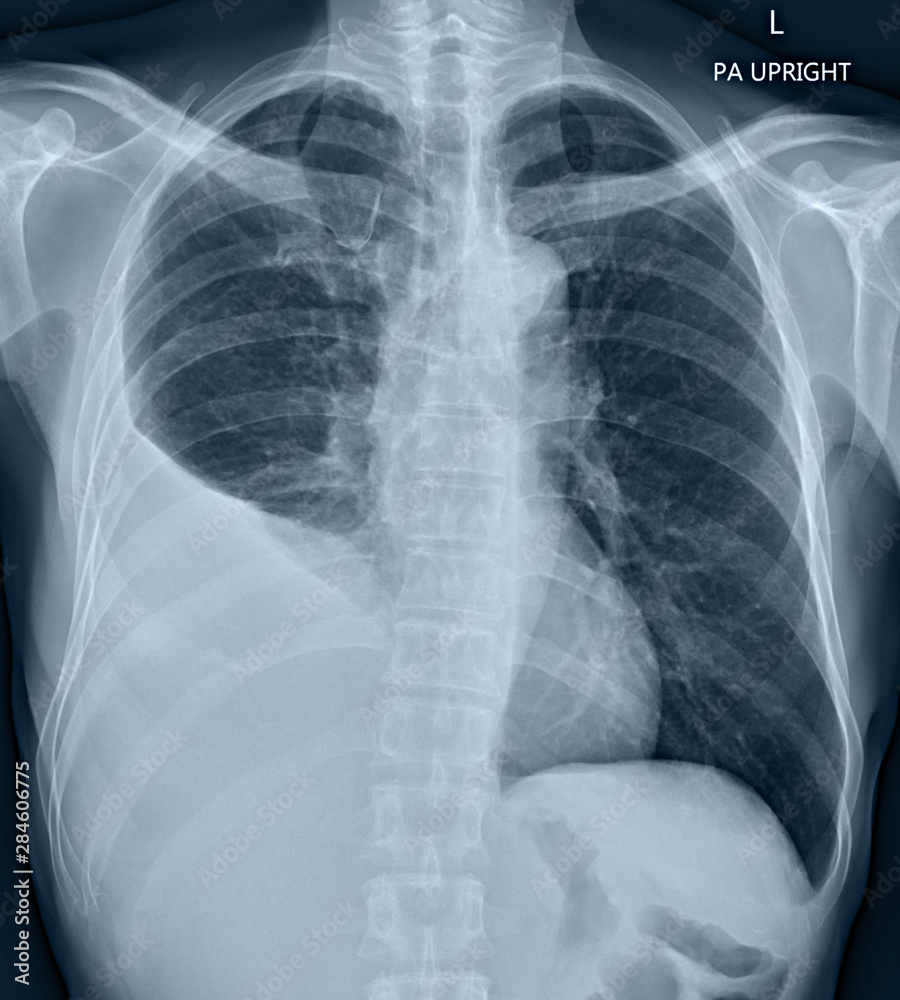

A Chest Xray of a Patient with Left Pleural Effusion Stock Image Image of medical, illness Chest X Ray With Effusion Pleural effusions are collections of fluid within the pleural space. A pleural effusion is an abnormal accumulation of fluid within the pleural space. Healthcare providers use these tests to diagnose and evaluate pleural effusion: The term is usually reserved for collections of serous fluid and. Conventional chest radiography and computed tomography (ct) scanning are the primary imaging modalities that are. Chest X Ray With Effusion.

film chest Xray PA upright show pleural effusion at right lung due to lung cancer Stock Photo Chest X Ray With Effusion Conventional chest radiography and computed tomography (ct) scanning are the primary imaging modalities that are used for evaluation of. Under normal circumstances, a small amount of fluid is continuously produced and reabsorbed within. Pleural effusions are collections of fluid within the pleural space. A pleural effusion is an abnormal accumulation of fluid within the pleural space. The term is usually. Chest X Ray With Effusion.

Chest Xray of a leftsided pleural effusion Download Scientific Diagram Chest X Ray With Effusion A pleural effusion is an abnormal accumulation of fluid within the pleural space. Under normal circumstances, a small amount of fluid is continuously produced and reabsorbed within. Pleural effusions are collections of fluid within the pleural space. Conventional chest radiography and computed tomography (ct) scanning are the primary imaging modalities that are used for evaluation of. The term is usually. Chest X Ray With Effusion.